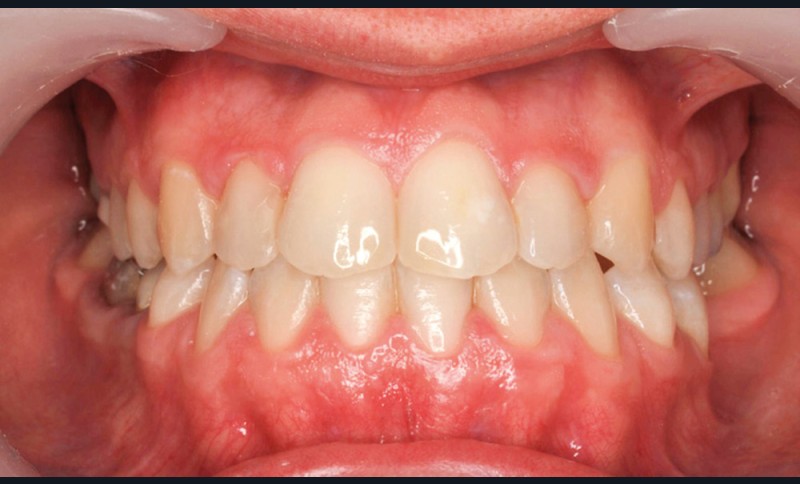

- Septième rendez-vous : les appareils sont déposés. Une empreinte numérique est prise pour réaliser trois aligneurs afin de parfaire le résultat occlusal et esthétique (fig. 3a-h).

Finalement, les aligneurs permettent les ajustements occlusaux fins et précis de finition.

- nivellement, alignement, établissement de la forme d’arcade sont obtenus majoritairement avec l’appareil lingual et finalisés avec quelques aligneurs ;

- contrôle du torque et angulation sont obtenus intégralement avec le multi-attache lingual à slots horizontaux, les finitions du torque et de l’angulation étant peu fiable par aligneurs ;

- les rotations sont corrigées à 95 % avec l’appareil lingual et finalisées avec quelques aligneurs.

Les finitions par aligneurs évitent les élastiques verticaux et les mouvements parasites sur les dents adjacentes lors de pliages de finition